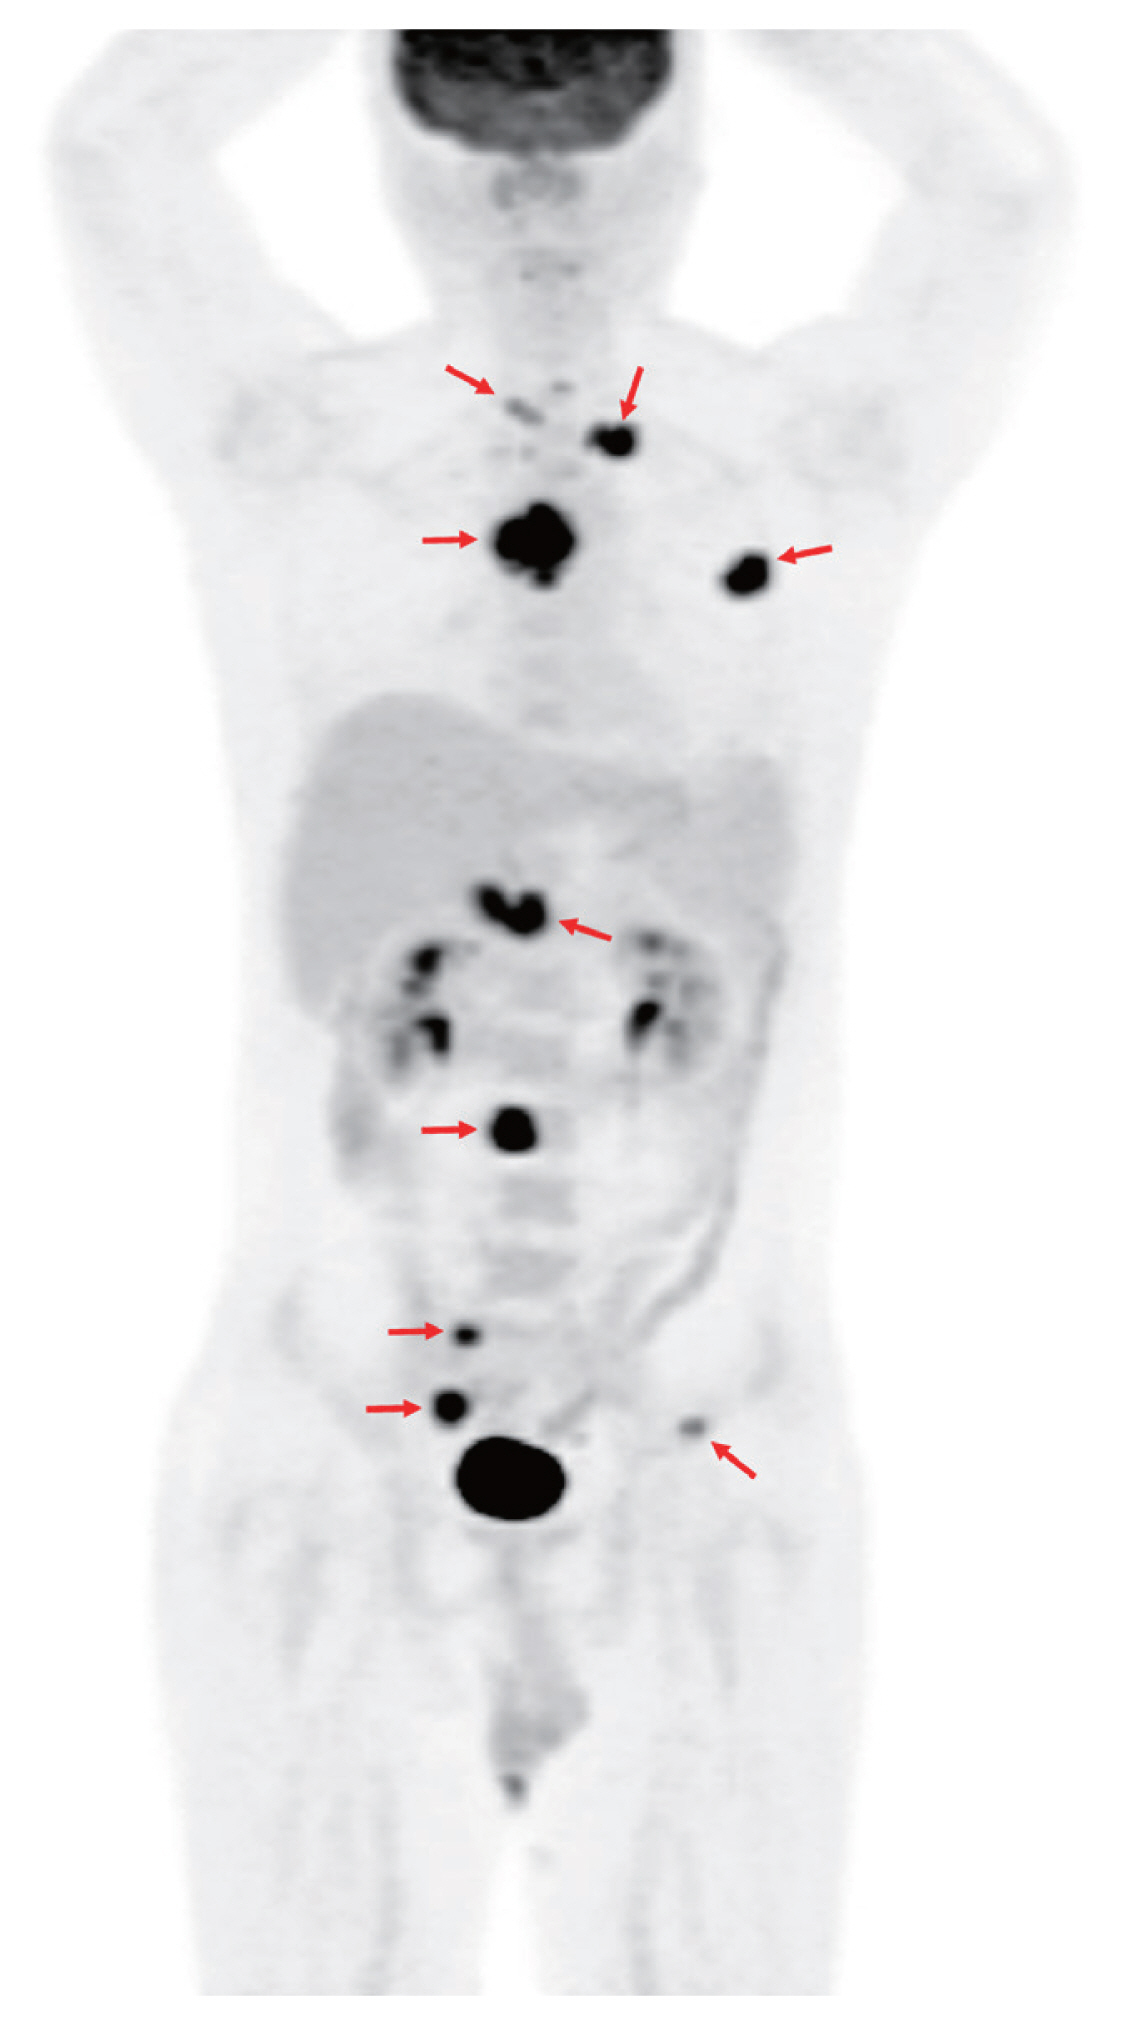

A 32-year-old man without underlying diseases presented to the emergency department with an abrupt onset of gait disturbances and a 4-week history of back pain. The patient was afebrile, and all laboratory findings were normal. Rapid plasma reagin test for syphilis was negative. Whole-spine magnetic resonance imaging revealed an abnormal signal intensity with contrast enhancement at levels T3-T5 and level L3 (Fig. 1), as well as in the right sacral alar portion and left second rib (not shown). However, chest computed tomography (CT) showed no abnormalities in the lung parenchyma, airways, pleura, or lymph nodes. Bone scan suggested bone metastases in the skull, left clavicle, left third rib, and T3-T5 and L3 vertebrae. 18F-fluorodeoxyglucose (18F-FDG) positron emission tomography/CT showed intense FDG uptake in multiple bone lesions and portocaval areas, possibly bone metastases and metastatic lymphadenopathy (Fig. 2). Percutaneous transpedicular bone biopsies were performed in the T4 and L3 vertebral bodies. Histopathological findings revealed chronic granulomatous inflammation with necrosis; however, acid-fast bacilli staining and duplex real-time polymerase chain reaction for Mycobacterium tuberculosis complex and non-tuberculous mycobacteria from fresh bone tissue were negative. On the fifteenth day after the biopsy, the mycobacterial culture from the bone specimens tested positive for M. tuberculosis complex.